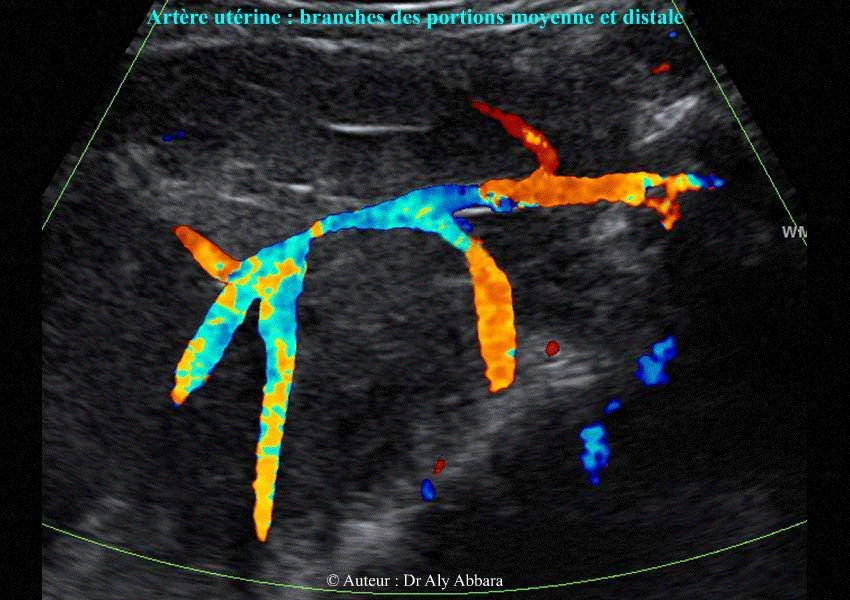

Artère utérine - Les branches des portions moyenne et terminale

Image échographique animée montrant les branches des portions

moyenne et terminale d'une artère utérine

Auteur : Dr Aly Abbara